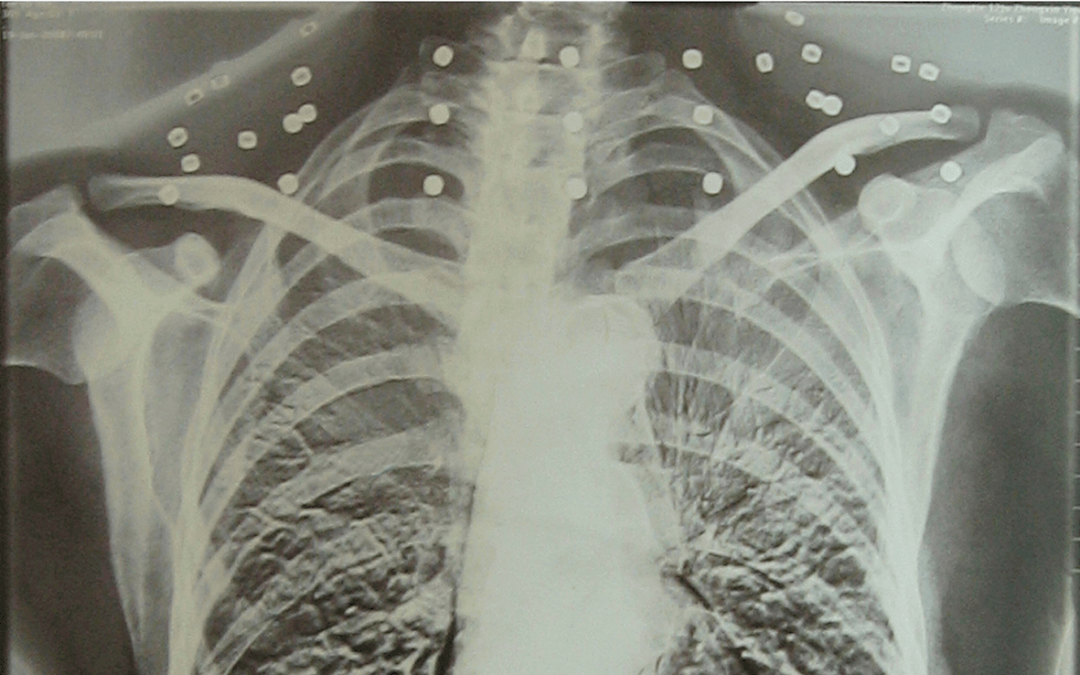

这张照片

是今年82岁的吴以先老人

拍摄的一张CT照

吴以先的颈部和腹部

共分布着33枚弹片

皇冠登一登二登三区别他体内的弹片都没有取出

身体留有弹片的位置就有痛感

但吴以先不考虑取出弹片

在皇冠登一登二登三区别他看来

这是皇冠登一登二登三区别他与战友并肩作战的见证

是皇冠登一登二登三区别他的勋章